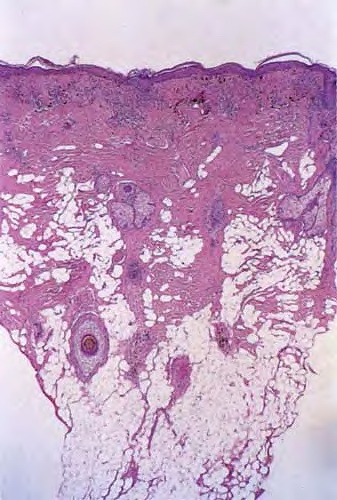

Discoid LE= الذئبة الحمامية القرصية